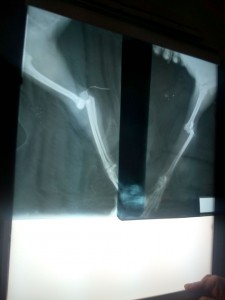

El pequeño mañana lo operan,va mejorando le van a poner los clavos en su patita Por Nuestros Hermanos Sin Voz A C atendiendo a los animalitos,sigue en la veterinaria no está hací dentro de la jaula tiene suero se le retira más tarde ahí va el perrito mañana esperamos todo salga bien

Cuantos animalitos hay en está situación y nadie lo ayuda, vino mi vecina muuuuy nerviosa me llamo Yola hay un perrito Abandonado y mal fuimos corriendo,unchico me ayudó lo llevamos a un veterinario solo le puso un tranquilizante empezó el recorrido fui con otro Sr me ayudó a cargarlo ni un Taxi me quisó recoger con el perrito,caminando ninguna veterinario me quería atender me acordé de un Doc y el me lo está atendiendo este perrito estaba tirado. El perrito, esta en el veterinario y mañana se opera, se le colocara 2 clavos, les estare informando el día de mañana.